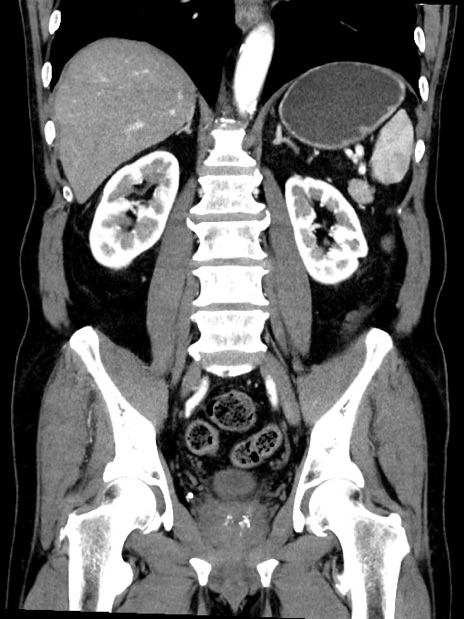

症例35(冠状断像)

【症例】70歳代 男性

【主訴】腹部膨満、嘔吐

【現病歴】昨日より腹部膨満感出現。本日増悪し、仙痛出現。嘔吐あり、受診。

【既往歴】糖尿病、胆摘後

【身体所見】BP 149/80mmHg、HR 74/min、BT 35.9℃、腹部:膨満、軟、圧痛なし。腸雑音減弱あり。上腹部正中切開瘢痕あり。

【データ】WBC 13500、CRP 1.72